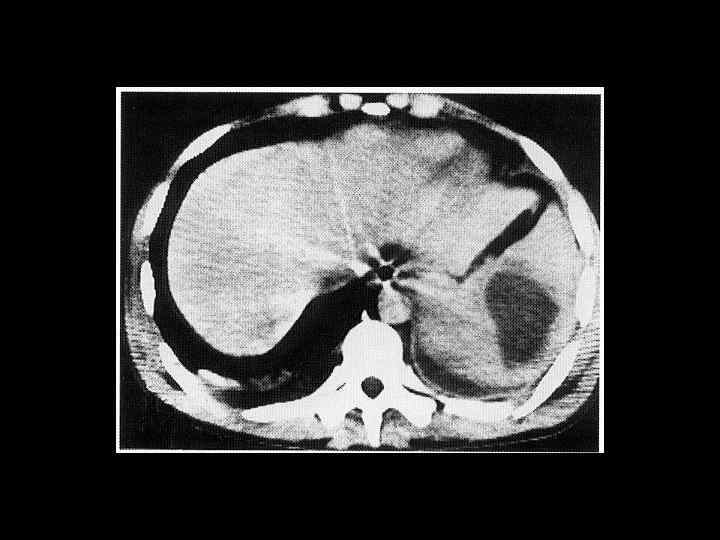

АКТУАЛЬНЫЕ ВОПРОСЫ РЕНТГЕНОЛОГИИ ЛУЧЕВАЯ ДИАГНОСТИКА ЗАБОЛЕВАНИЙ СЕЛЕЗЕНКИ Опухолевое поражение селезенки